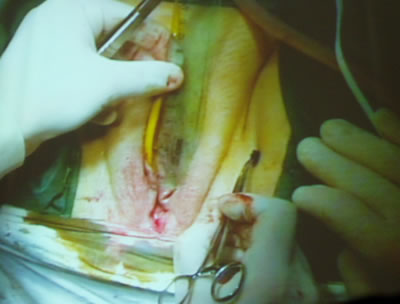

Профессор отмерил линейкой расстояние на котором он будет

проводить вколы для проведения синтетической петли.

Отметил бриллиантовой зеленью места входа инструмента для

трансобтураторного слинга.

Отдельным разрезом на средине расстояния длинника уретры,

оператор рассек отдельным разрезом слизистую влагалища и

приступил ко второму этапу операции – трансобтураторному

слингу